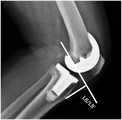

FIG. 5 is a fourth schematic diagram of a knee joint line using the deep learning-based pre-revision surgery planning method after total knee replacement provided by the present invention;

4. The change of the joint line before and after the revision is measured by taking the medial femoral condyle plane and the tibial tubercle as reference parts.

As shown in FIG. 5, in the X-ray lateral side of the knee joint, 1 perpendicular line is drawn from the tibial tubercle to the line on the plane of the posterior medial femoral condyle. The vertical line segment is a joint line, and the length of the vertical line segment is the length of the joint line. The anterior and posterior joint line lengths for revision are designated L8 and L8', respectively. The length of the joint line is L8-L8'. In fig. 5, L8 and L8' are used as examples only, and do not represent that the joint line before and after revision must be the same.